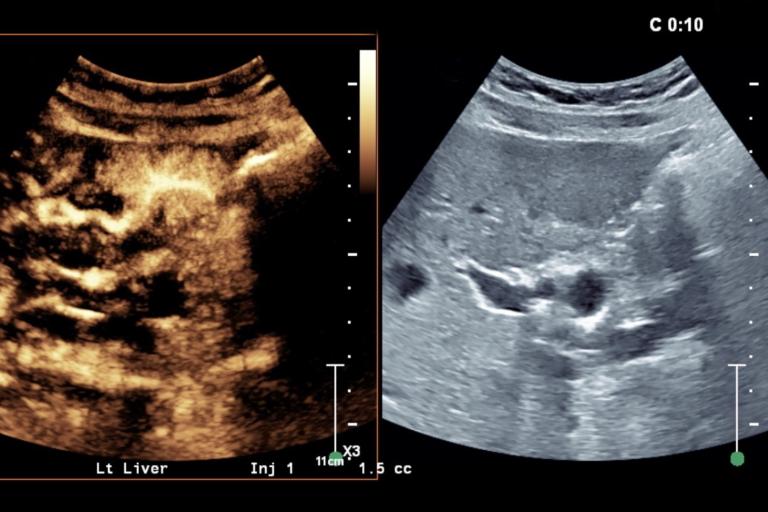

- HCC diagnosis and response to therapy

- Quantitative contrast-enhanced ultrasound for organ and tumor perfusion analysis

- Contrast-enhanced ultrasound motion correction and frame filtering